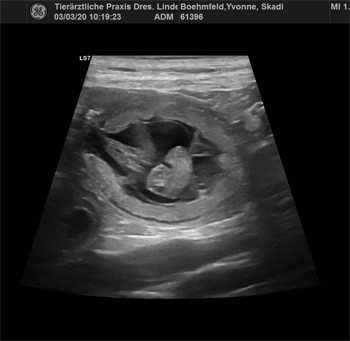

03.03.2020 Riesenfreude über kleine Herzchen Nach einem sehr emotionalen Wochenende war heute der Ultraschall für den U-Wurf. To keep a long story short:

|